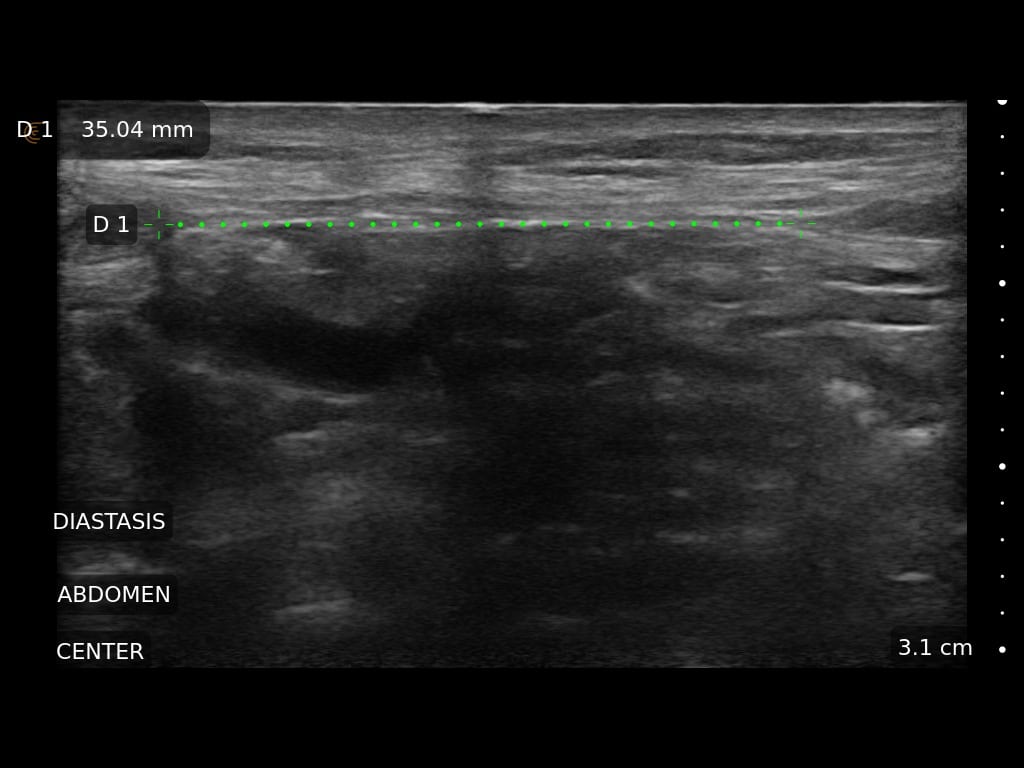

Ultrasound Imaging is very useful clinical tool to assess patient’s anatomy. In the past, ultrasound imaging was done primarily by radiologists, but is now being employed by many clinical specialties. Ultrasound use by Plastic Surgeons, however, is relatively new. Dr. Wigod has found ultrasound imaging to be a particularly valuable addition to physical exam and provides this service to his patients. Ultrasound imaging is especially useful to assess breast implants for problems such as ruptures, capsular contracture, and fluid collections. Dr. Wigod also uses ultrasound to examine other body areas and to help guide nerve blocks. Surgeon performed ultrasound does not replace radiologist performed imaging and is not for cancer screening.